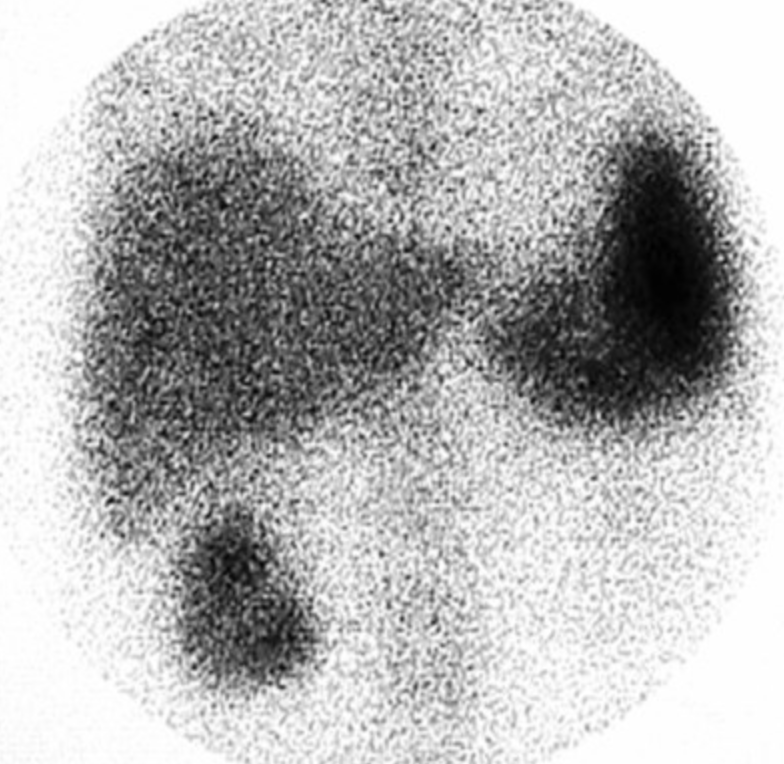

Normal Study